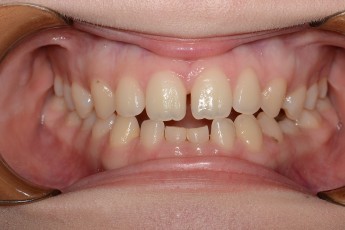

BEFORE & AFTER

- 덧니교정